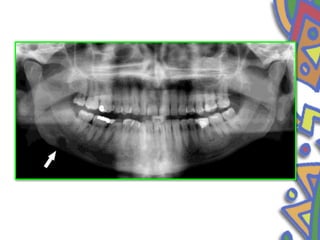

• Stafne bonedefect • First described by Stafne in 1942 • The exact pathogenesis is still obscure. • Epidemiology • Men in their • fifth or seventh decade of life

• 55.

• Stafne suggestedthat the cavity could result from a failure of normal bone deposition in the region formerly occupied by cartilage . • localized pressure atrophy of the lingual surface of the mandible from the adjacent salivary gland

• 56.

• Clinical features •Present as asymptomatic radiolucency below the mandibular canal in the posterior mandible between the molar and angle of mandible • well circumscribed • sclerotic border

• 57.

• Superimposed overthe apices of anterior teeth • Stable in size • 1 to 3cm in diameter • below the inferior dental canal • Incidental • d/d